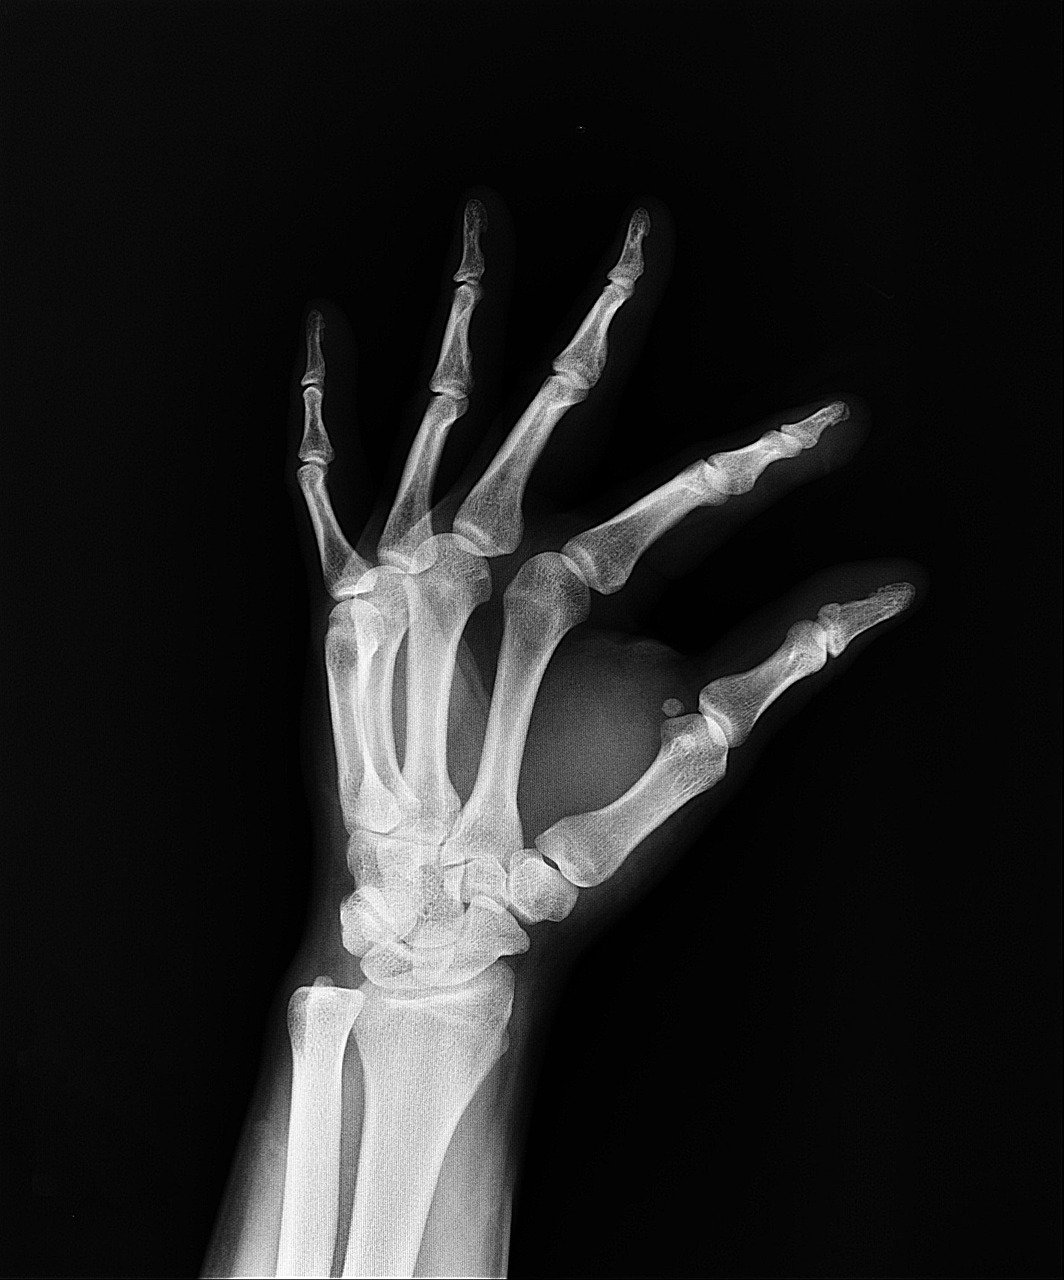

L’un des domaines où l’impact est le plus spectaculaire reste sans conteste l’imagerie. Les algorithmes de vision par ordinateur, entraînés sur des banques d’images gigantesques, agissent désormais comme une seconde paire d’yeux infatigable pour les radiologues. Là où l’œil humain peut fatiguer après des heures d’analyse de clichés IRM ou de scanners, le système maintient un niveau de vigilance constant, capable de repérer des anomalies microscopiques invisibles à l’œil nu.

Les réseaux de neurones profonds ont permis de faire un bond en avant considérable dans l’oncologie. En comparant une mammographie ou une radiographie pulmonaire à des millions de cas précédents, l’intelligence artificielle peut identifier des signaux faibles précurseurs de lésions malignes. Cette capacité permet d’intervenir à des stades beaucoup plus précoces, augmentant drastiquement les chances de guérison. Il ne s’agit plus seulement de voir la maladie, mais de la caractériser avec une fiabilité qui avoisine désormais les 99% pour certaines pathologies spécifiques.

Cette technologie ne remplace pas le praticien, mais elle lui offre un filet de sécurité indispensable. Le médecin peut se concentrer sur les cas complexes et la stratégie thérapeutique, laissant à la machine le soin de réaliser le tri initial et le repérage volumétrique des lésions. C’est une collaboration qui a permis de désengorger de nombreux services de radiologie qui étaient au bord de la rupture au début de la décennie.